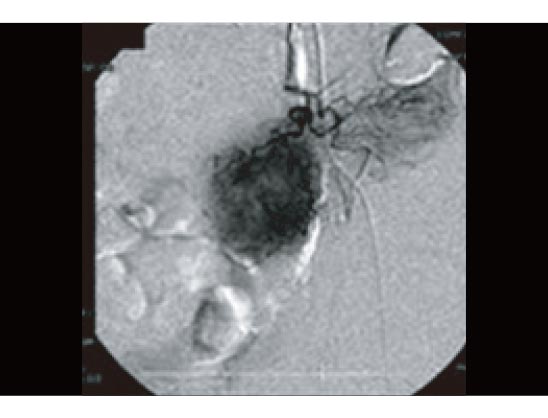

免疫治療前のCT検査

下の画像は、治療前に血管カテーテルによって大腸がんそのものを調査した画像です。がん細胞の回りを取り囲むがんの新生血管が良く観察できます(丸く、黒々と染まった部分)。この時点での残り余命判断は非常に厳しいものでした。およそ1ヶ月程度。それも大きな急変が無ければ、が条件です。即時入院、そして生存して病院を退院することが想定されない末期的状況と言える状態でした。